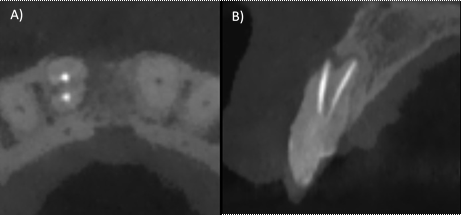

In the second appointment, the irrigation protocol was performed again, the canals were dried with sterile paper tips and obturated with continuous wave technique (Fast fill and Fast Pack, Eighteeth Medical) and AH-Plus cement (Dentsply Maillefer, Switzerland) (Fig. 3 B-C). Finally, flowable resin was used for sealing the coronal access. A second CBCT was requested to evaluate the correct localization and obturation of the dental organ (Fig. 4 A-B).

Figure 2: A) Axial section of the CT scan, two roots belonging to dental organ #11 are observed, the vestibular root shows obturation material, but the palatal root was not treated, B) Sagittal section where a permeable palatal canal can be seen.